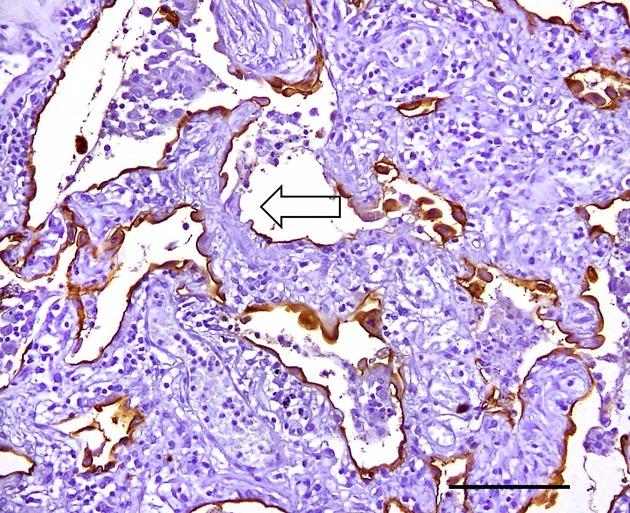

Pneumocyte injury is a characteristic of pulmonary interstitial pneumonias (IPs). Histological markers of pneumocyte injury and inflammation include pneumocyte necrosis, erosion, hyaline membrane and fibrin exudation with subsequent intraluminal granulation tissue formation. We found that intracytoplasmic inclusions in pneumocytes are ubiquitin-positive (Ub(+) ) and that the number of Ub(+) pneumocytes shows positive correlation with the extent of diffuse alveolar damage (DAD). To determine the role of Ub(+) pneumocytes and inclusions in IPs, we studied their relationship with pathological and clinical features of DAD, usual interstitial pneumonia (UIP) and organizing pneumonia (OP), including airspace enlargement with fibrosis (AEF). We analysed Ub(+) pneumocytes, inclusions, erosions and intraluminal granulation tissue in relation to pneumocyte injury. The numbers of immunohistochemically identified Ub(+) inclusions in each IP were higher than the number of inclusions detected by light microscopy. The inclusions detected by Ub(+) immunostaining were identical to the inclusions observed by light microscopy. UIP and DAD had many Ub(+) inclusions, while OP and AEF had fewer Ub(+) inclusions. These results suggest that the extent of Ub(+) inclusions reflects the severity of pneumocyte injury among IPs. Thus, Ub(+) inclusions are a histological marker of pneumocyte injury that may be helpful in determining the severity and prognosis of IPs.

肺细胞损伤是肺间质性肺炎(IPs)的一个特征。肺细胞损伤和炎症的组织学标志物包括肺细胞坏死、糜烂、透明膜和纤维蛋白渗出,随后形成管腔内肉芽组织。我们发现肺细胞内的包涵体是泛素阳性(Ub(+)),并且Ub(+)肺细胞的数量与弥漫性肺泡损伤(DAD)的程度呈正相关。为了确定Ub(+)肺细胞和包涵体在IPs中的作用,我们研究了它们与DAD、普通间质性肺炎(UIP)和机化性肺炎(OP)的病理和临床特征的关系,包括伴有纤维化的气腔扩大(AEF)。我们分析了与肺细胞损伤相关的Ub(+)肺细胞、包涵体、糜烂和管腔内肉芽组织。每个IP中免疫组化鉴定的Ub(+)包涵体数量高于光学显微镜检测到的包涵体数量。通过Ub(+)免疫染色检测到的包涵体与光学显微镜观察到的包涵体相同。UIP和DAD有许多Ub(+)包涵体,而OP和AEF的Ub(+)包涵体较少。这些结果表明,Ub(+)包涵体的程度反映了IPs中肺细胞损伤的严重程度。因此,Ub(+)包涵体是肺细胞损伤的组织学标志物,可能有助于确定IPs的严重程度和预后。